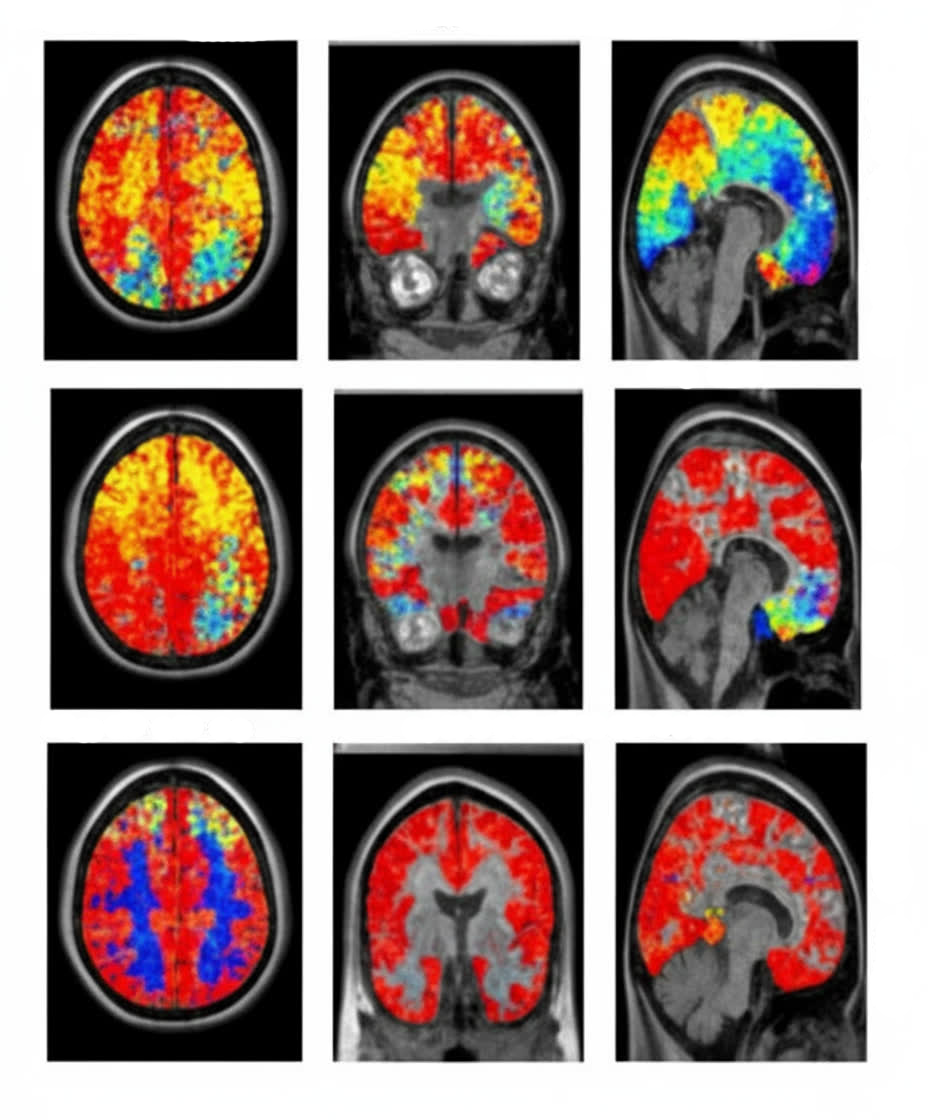

QEEG Brain Mapping & Quantitative Analysis

19-channel brain mapping provides objective data on cortical dysregulation, connectivity patterns, and frequency band abnormalities. Creates individualized training targets and tracks progress quantitatively.

- Objective verification through pre/post QEEG comparison